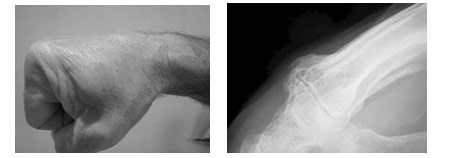

Le carpe « bossu » se définit par l’existence d’une tuméfaction dure, située à la base du 2e et 3e métacarpiens. Cette tuméfaction peut être acquise, plus fréquente chez la femme que l’homme, du côté dominant et survenant vers la quarantaine, dégénérescence arthrosique dont le « bec de perroquet » est palpable sous la peau. Certaines professions exposées ou certains sports (la boxe…) peuvent entraîner cette pathologie plus précocement.

Le motif de consultation est soit « esthétique » ; c’est l’aspect de la bosse qui dérange la patiente. Cette tuméfaction peut être aussi douloureuse par le conflit mécanique qu’elle entraîne avec les extenseurs voisins. Un kyste arthro-synovial peut aussi être associé.

Une radiographie standard face et surtout profil strict –voire comparatif- fait le diagnostic.